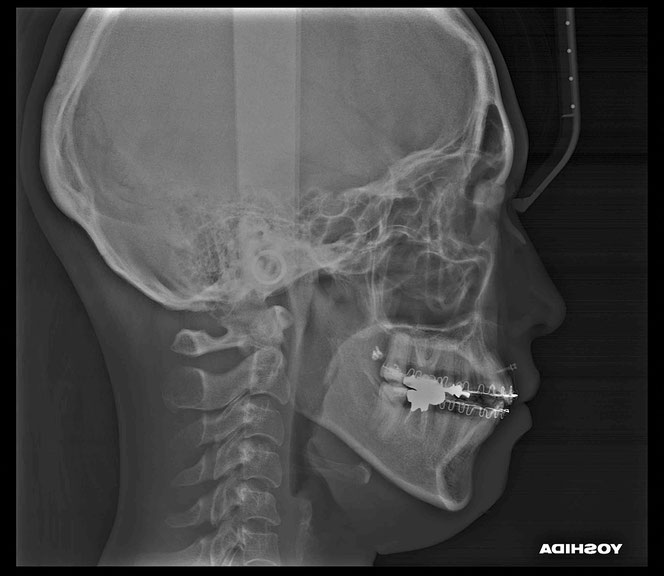

矯正治療後に奥歯の歯ぐきが2~3ミリ退縮。

その結果、露出した根の一部が虫歯になっていました。

治療後の変化

再生治療により、

2~3ミリ下がっていた歯ぐきが回復。

歯の長さが自然なバランスに戻り、

厚みのある丈夫な歯ぐきが再建されました。